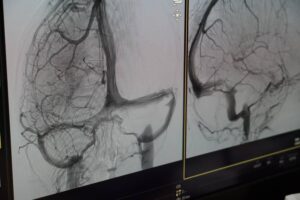

„Ca să ajungem în această fericită situație, de a avea un centru de tratare AVC, a trebuit, în primul rând, să reabilităm și să modernizăm spațiile medicale, apoi să achiziționăm aparatura necesară. Aici, la Sibiu, prin fonduri europene nerambursabile am adus tehnică medicală de ultimă generație, printre care și un angiograf performant, utilizat în intervențiile AVC, a cărui valoare a depășit șapte milioane de lei. Am avut și șansa ca doamna dr. Monica Mănișor, sibiancă la origine, să aleagă spitalul nostru, după ce a profesat o lungă perioadă la Spitalul Universitar din Strasbourg”, a declarat Daniela Cîmpean, președinta Consiliului Județean Sibiu.

Foto: Spitalul Clinic Județean de Urgență Sibiu